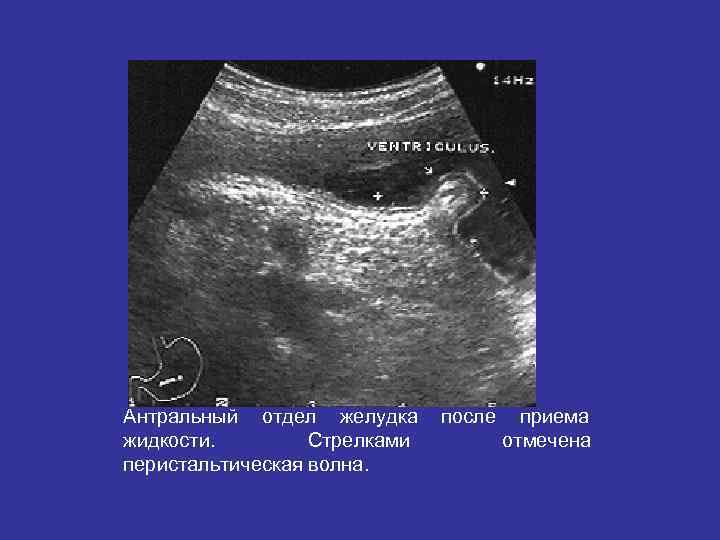

Антральный отдел желудка после приема жидкости. Стрелками отмечена перистальтическая волна.